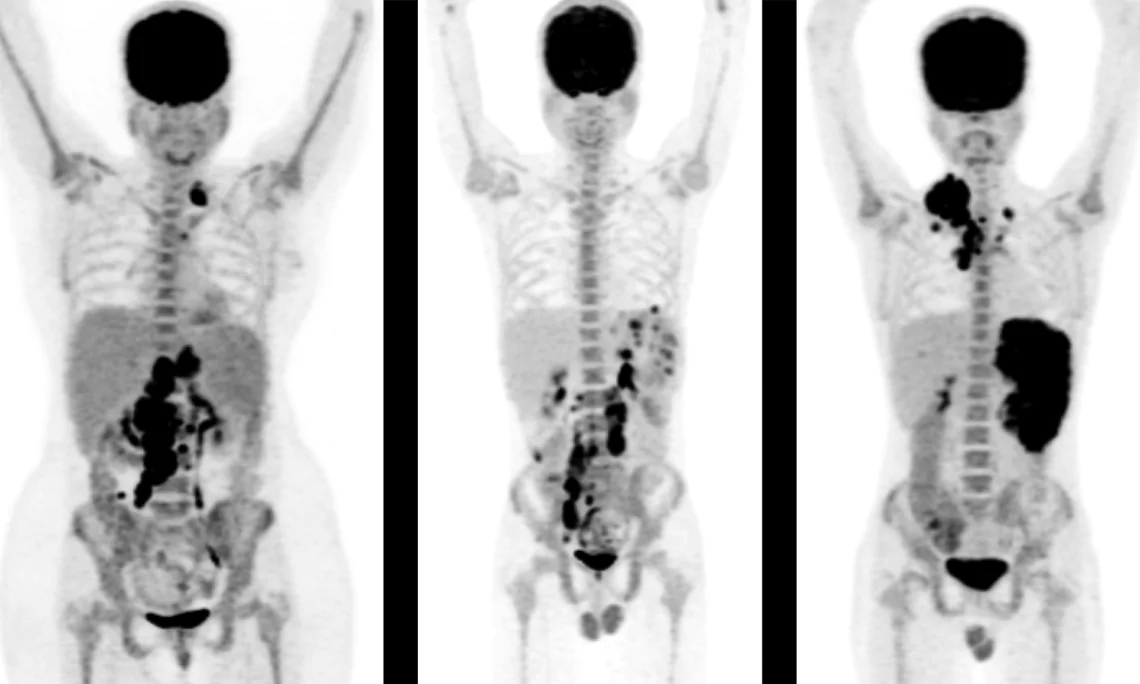

PET (Position Emission Tomography) is a nuclear medicine technique for evaluating biomedical and physiological processes in the body. The combination with CT scan adds anatomic information.

PET/CT